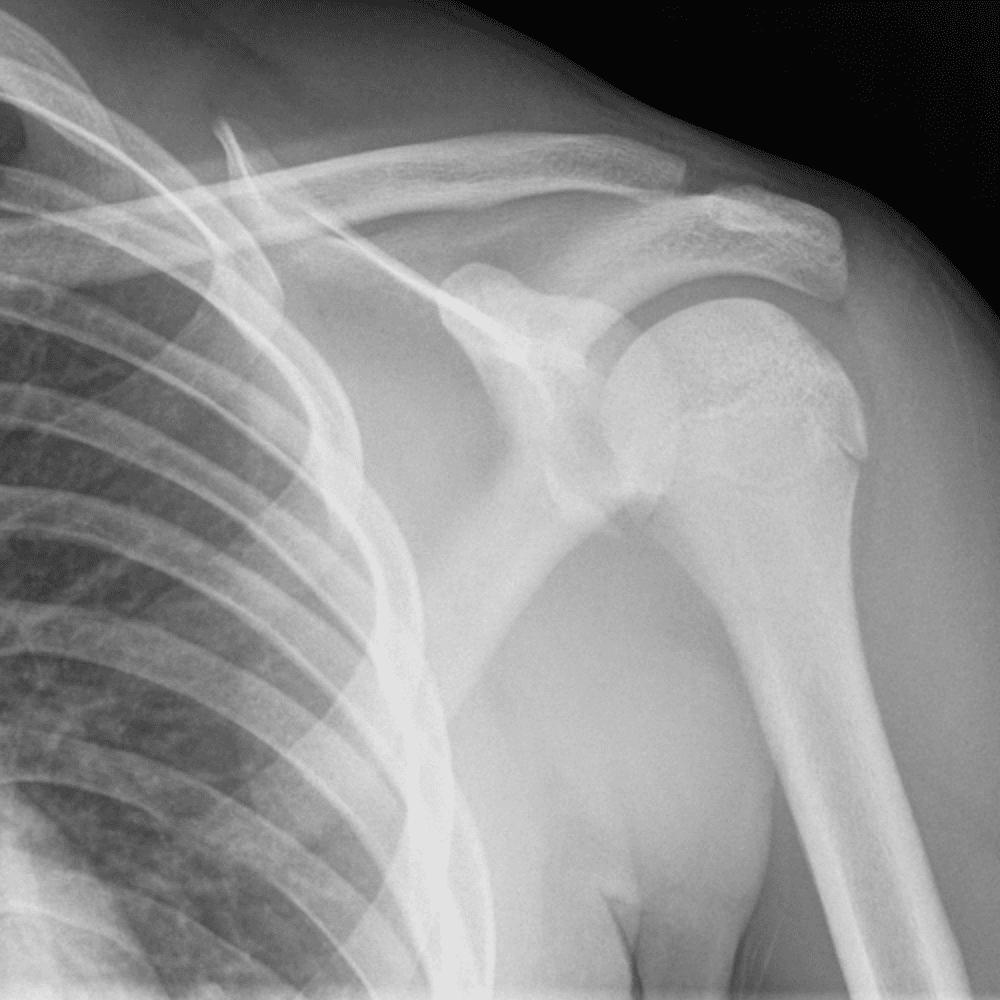

Simuliert den Dienst durch subtile oder schwierige Fälle und einige Normalbefunde.

30 Fälle